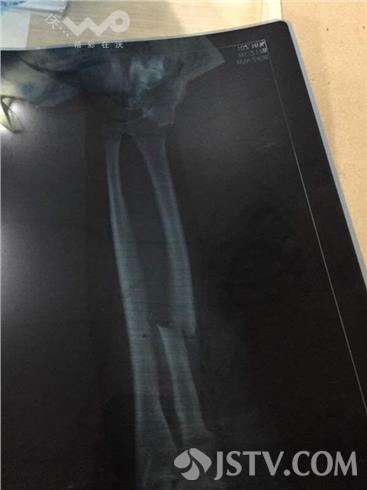

昨晚12点左右在南京栖霞区燕华花园一饭店因客人酒喝多了,与饭店老板发生纠纷后,客人去后场拿出菜刀将老板砍伤,并砸了2台轿车,后市民报警,随后警方将其控制,目前警方正在调查。